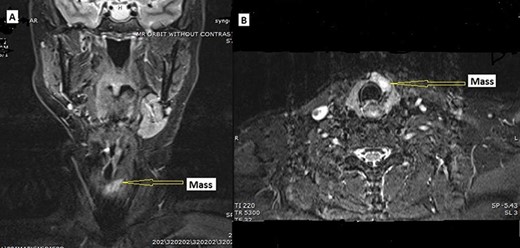

A 58 y/o F with a history of a right carotid body tumor 13 years ago, and a right vagal PG 24 years ago status post excision presented with a thyroid nodule. The patient family history is significant for carotid body tumor in her brother; physical examination was unremarkable with no palpable neck masses or lymph nodes except for nodule. Serum TSH, FT3 and FT4 were consistent with euthyroid state, and serum calcitonin was normal. Thyroid ultrasonography showed a dominant solid hypoechoic nodule in the isthmus extending into the left lobe (24 × 8 × 23 mm), with associated margin and increased central and peripheral vascularity w/o calcification. Further workup with magnetic resonance imaging (MRI) demonstrated hyperintense mass lesion within the isthmus extending into the left thyroid lobe (Fig. 1A and B). CT scan of the chest, abdomen and pelvis were negative. Fine needle aspiration biopsy of the nodule revealed atypia of undetermined significance.

MRI. (A) Coronal and (B) axial, STIR image demonstrating hyperintense mass lesion (arrow pointing) within the isthmus extending into the left thyroid lobe.